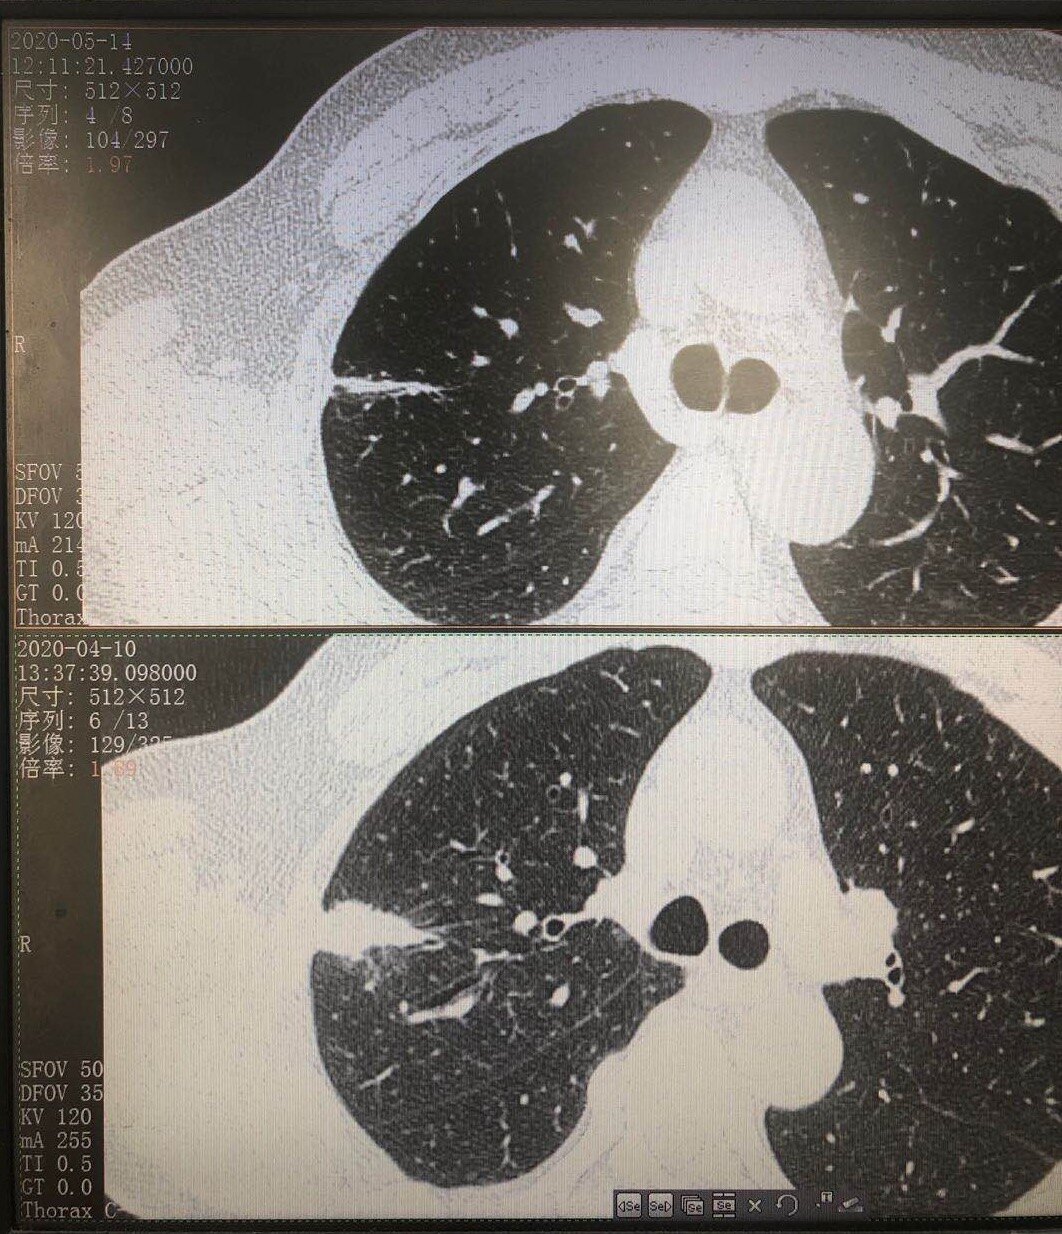

随访进展的肺多发实性结节会是啥

图片尺寸512x512

结核球:球形高密度结节,边缘平整,未见明显毛刺,病灶周围可见卫星灶